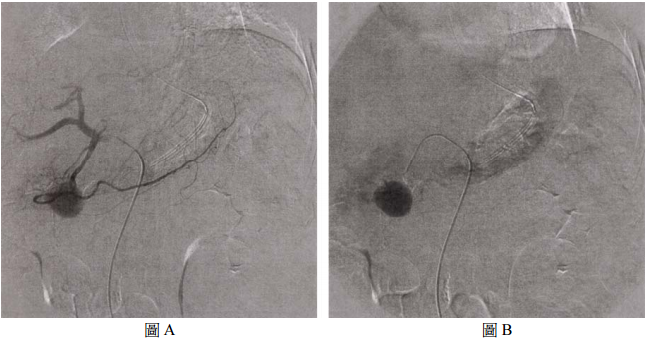

74 曾先生有 35 年喝酒病史,過去三年內有兩次急性胰臟炎發作,最近三星期,因持續解黑便,胃十二 指腸動脈攝影如圖 A 和 B,最合理的診斷為 anterior superior pancreaticoduodenal artery 的: (A)阻塞(occlusion) (B)假性動脈瘤(pseudoaneurysm) (C)動靜脈瘻(arterio-venous fistula) (D)動靜脈畸型(arterio-venous malformation)